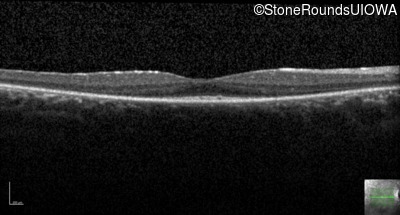

AR Retinitis Pigmentosa (IA1aiii)

Age at visit: 24 years

This 24 year old woman first noticed difficulty tracking a volleyball when she was 15 years old. More recently she has been reluctant to go running because of her constricted visual field inferiorly. She did not have any nyctalopia when she was first symptomatic but has developed it more recently.

AR Retinitis Pigmentosa USH2A Cys759Phe TGC>TTC Glu4304 del1gA AR